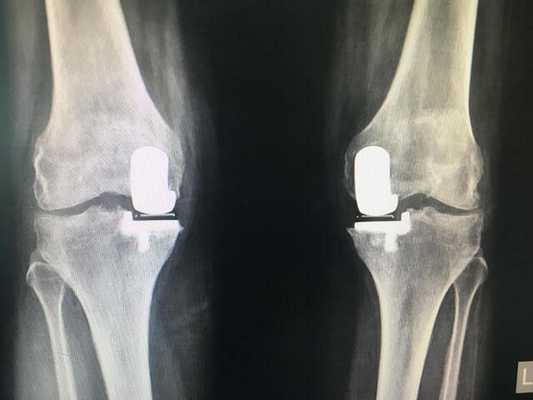

Если сустав поражен указанным на изображении образом, то возможна его частичная замена.

Основной метод лечения – постановка эндопротеза вместо поврежденного сустава. Раньше выполнялось преимущественно тотальное эндопротезирование коленного сустава, однако сейчас активно развивается другое направление – одномыщелковое (частичное) эндопротезирование.

Имплант на рентгене.